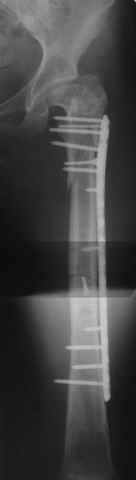

Прошу прощения, со снимками глюк произошел. Высылаю. С уважением Евгений У.

Получилось очень симпатично, мои поздравления. А можно фото конечности без наклеек посмотреть?

И межфрагментарный винт на диафизе - так ли он нужен при выбранном варианте остеосинтеза с относительной стабильностью?

Хотя все-таки закрыто антгерадно заштифтовать тут было вполне можно, и при использовании отечетственного имплантата лечение обошлось бы на порядок дешевле. Опасения коллеги Кульджанова насчет кровоснабжения головки бедра и предстоящих операции в этой области кажуься несколько

преувеличенными - и стержень можно через вертел ввести, да и расстройства кровоснабжения головки, если они случатся после штифтования, не будут длиться вечно.

Но в люом случае, что сделано - то сделано, и сделанное выглядит вполне обнадеживающе, так что еще раз поздравляю коллег с успешным выходом из непростой ситуации.